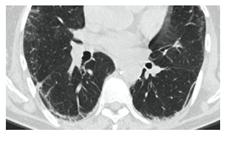

2. Наличие клинических проявлений, указанных в п. 1, в сочетании с характерными изменениями в легких по данным компьютерной томографии (КТ) (см. Приложение 1 настоящих рекомендаций) вне зависимости от результатов однократного лабораторного исследования на наличие РНК SARS-CoV-2 и эпидемиологического анамнеза.

- Изменения при КТ (рентгенографии), типичные для вирусного поражения (объем поражения минимальный или средний; КТ 1-2)

- Изменения в легких при КТ (рентгенографии), типичные для вирусного поражения (объем поражения значительный или субтотальный; КТ 3-4)

- Изменения в легких при КТ (рентгенографии), типичные для вирусного поражения критической степени (объем поражения значительный или субтотальный; КТ 4) или картина ОРДС.

КТ имеет высокую чувствительность в выявлении изменений в легких, характерных для COVID-19. Применение КТ целесообразно для первичной оценки состояния ОГК у пациентов с тяжелыми прогрессирующими формами заболевания, а также для дифференциальной диагностики выявленных изменений и оценки динамики процесса. КТ позволяет выявить характерные изменения в легких у пациентов с COVID-19 еще до появления положительных лабораторных тестов на инфекцию с помощью МАНК. В то же время, КТ выявляет изменения легких у значительного числа пациентов с бессимптомной и легкой формами заболевания, которым не требуется госпитализация. Результаты КТ в этих случаях не влияют на тактику лечения и прогноз заболевания при наличии лабораторного подтверждения COVID-19. Поэтому массовое применение КТ для скрининга асимптомных и легких форм болезни не рекомендуется.